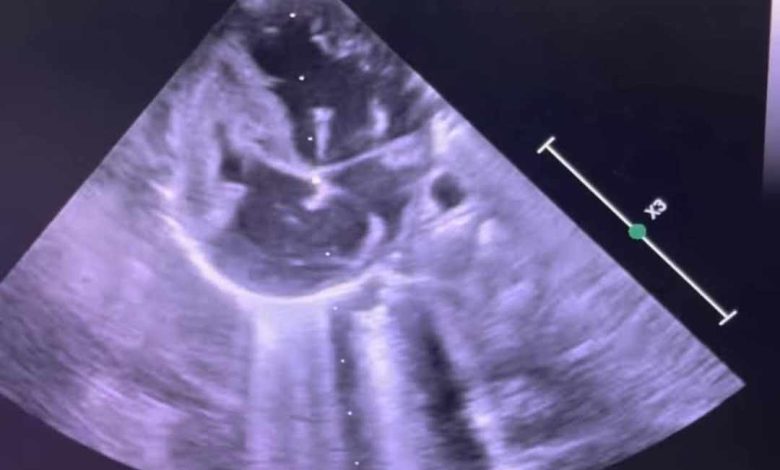

شهدت مستشفى أطفال مصر للتأمين الصحي إنجازًا طبيًا جديدًا يضاف إلى سجلها الحافل في رعاية الأطفال حديثي الولادة، حيث نجح الفريق الطبي بالمستشفى في إجراء أول عملية توسيع للصمام الأورطي بالبالون عن طريق القسطرة لطفلة حديثة الولادة تبلغ من العمر شهرين وتزن 3.600 كجم .

كانت الطفلة تعاني من ضيق شديد بالصمام الأورطي مما تسبب لها في نهجان شديد عند الرضاعة أثر على نموها الطبيعي، حيث تمت العملية الدقيقة بنجاح كبير، وتم نقل الحالة إلى الرعاية المركزة لاستكمال العلاج والمتابعة الطبية، وتتمتع الطفلة الآن بحالة صحية مستقرة وتستعد للخروج والمتابعة الدورية في العيادات الخارجية.